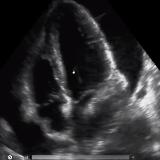

- Case of Subdural Spread of Injected Local Anaesthesia in a Patient with Selective Transforaminal Cervical Nerve Root Block

Although uncommon, selective cervical nerve root blocks can have serious complications. The most serious complications that have been reported include cerebral infarction, spinal cord infarction, transient quadriplegia, and death. This report highlights a case of a patient who had taken local anesthesia that spread to the subdural region causing ac